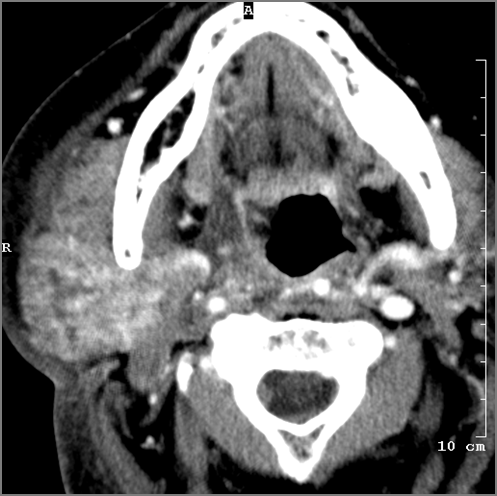

There is general or localized soft tissue swelling of the superficial or deep neck soft tissues.

There is edema/abscess within or surrounding the buccal space, masticator space, floor of the mouth, submandibular space or the adjacent superficial fascia or subcutaneous fat and skin.

The parotid, submandibular and sublingual glands are enlarged.

The parotid, submandibular and sublingual glands do show abnormal enhancement.